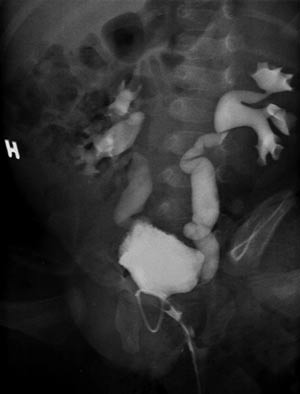

Pasient 1. En fire uker gammel gutt ble innlagt pga. manglende vektøkning. Det var ikke rapportert noe unormalt ved ultralydkontroll i svangerskapet. Han var født til termin, fødselsvekten var 4 100 g. Etter utskrivning fra barselavdelingen hadde det vært litt ammeproblemer. Han fikk derfor melk fra flaske, ifølge moren i adekvat mengde. Vekten ved innkomst var 3 895 g. Han virket slapp og medtatt, men sirkulasjonen var god og blodtrykket normalt. Man fikk inntrykk av at scrotum var litt pigmentert, men penis var normal av størrelse. Blodprøver ved innkomst er oppsummert i tabell 1. Ut fra kliniske funn og blodprøver mistenkte man adrenogenitalt syndrom, salttapende form. Han fikk derfor første døgn intravenøs væskebehandling med glukose 50 mg/ml tilsatt 20 mmol NaCl, tilsvarende NaCl 5 mmol/kg/døgn. Det ble deretter startet substitusjonsbehandling med kortison og mineralkortikoid samt gitt peroralt salttilskudd. Elektrolyttverdiene ble normalisert i løpet av få dager. Prøvesvar viste imidlertid normalverdier for 17-OH-progesteron og andre forstadier til binyrebarkhormoner. Det ble så gjort en abdominal ultralydundersøkelse, som viste normalt store binyrer, men bilateral hydronefrose og hydroureter. Det var også pyuri og vekst av gule stafylokokker i urinen, selv om pasienten nå hadde fin vektøkning, var i god allmenntilstand og hadde normale infeksjonsprøver. Han fikk antibiotikabehandling mot urinveisinfeksjonen. Omtrent samtidig kom det svar fra hormonlaboratoriet om at aldosteronverdien var kraftig forhøyet (tab 1), forenlig med pseudohypoaldosteronisme. Som ledd i videre utredning ble det ved miksjonsuretracystografi påvist bilateral vesikoureteral refluks grad 3 – 4 (fig 1). Han har senere fått antibiotikaprofylakse. Man fortsatte med peroralt salttilskudd i ca. fem uker. Ved oppfølging forble Na- og K-verdiene normale. Fire uker etter innleggelsen var aldosteronverdien normalisert og han viste fin vekst og trivsel.